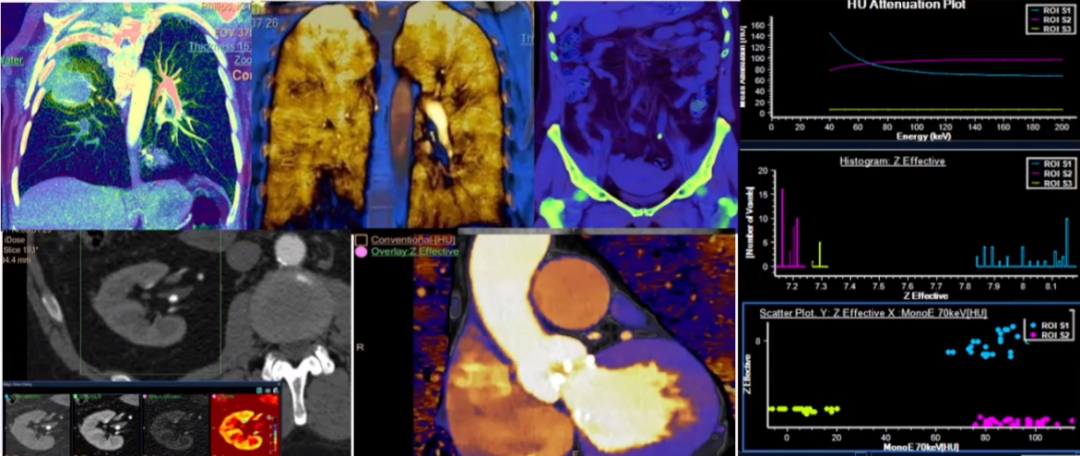

区别于其他能谱CT,皓克光谱CT真正在临床上实现了能量扫描的检查流程常规化、图像显示多元化、分析数据光谱化、临床诊疗精准化。一切扫描皆能量,使日常操作更加便捷。只需一次扫描,即可得到传统CT图像以及能谱曲线图、有效原子序数图、碘密度图、尿酸图等16大类多维度的功能影像信息数据,并适用于任何临床应用场景,可以更好、更快、更精准的发现病变、诊断病变,实现更多的临床突破。